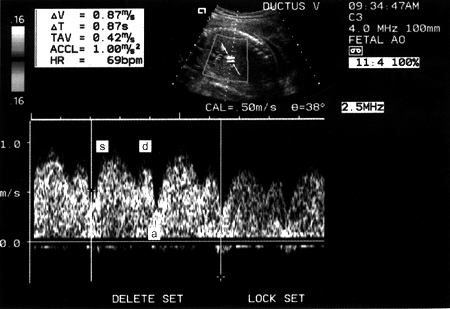

Εικόνα 2. Παθολογική Doppler κυματομορφή του φλεβώδη πόρου με αναστροφή του κύματος "a".

Στην υπολειπόμενη, όμως, ανάπτυξη που σχετίζεται με εμβρυική υποξία, οι ανωμαλίες του φλεβώδους πόρου στη Doppler υπερηχογραφία χαρακτηρίζονται από αύξηση της αντίστασης στη ροή του φλεβικού αίματος, με προοδευτική επιπέδωση του a κύματος που προσεγγίζει τη βασική γραμμή, ή με ανεστραμμένο το a κύμα. Το ανεστραμμένο a κύμα του φλεβώδους πόρου αποτελεί ισχυρό προγνωστικό παράγοντα περιγεννητικής νοσηρότητας και θνησιμότητας, γεγονός που επιβάλει την άμεση διεκπεραίωση του τοκετού(23,24) (εικόνα 2).